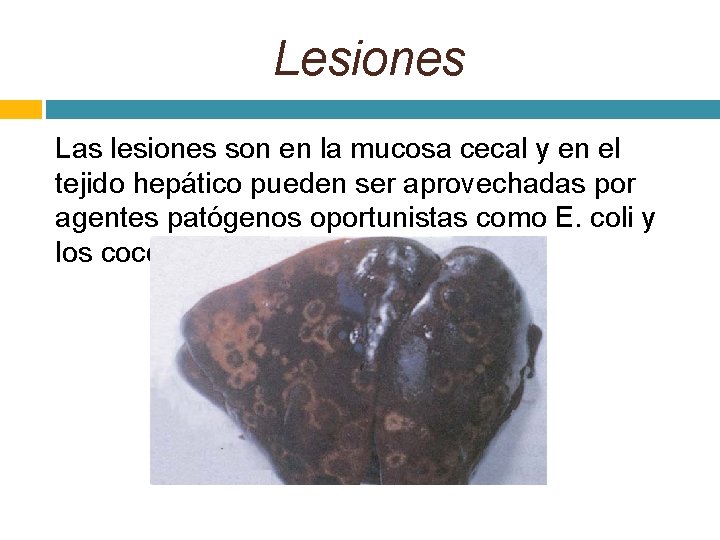

Lesiones Las lesiones son en la mucosa cecal y en el tejido hepático pueden ser aprovechadas por agentes patógenos oportunistas como E. coli y los coccidios.